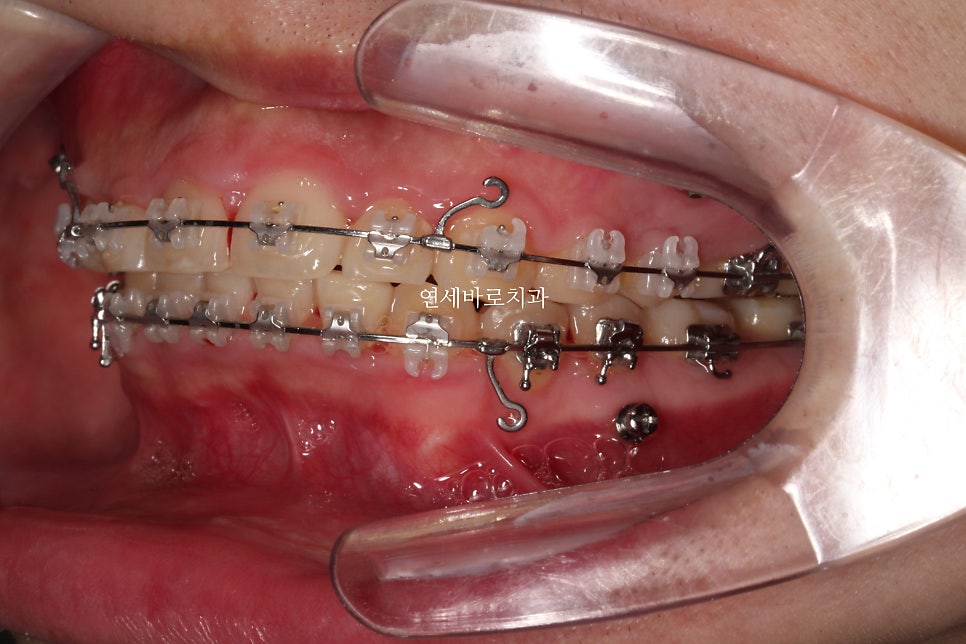

어느정도 준비를 하는 배열의 시간이 지나가고 #미니스크류 를 식립했습니다.

환자분의 골격상태 등을 고려하여 진단했고, 미니스크류를 많이 심진 않았습니다.

위쪽은 2개 심고 치료를 마무리 했습니다.

아래쪽은 중심선을 맞추기 위해 편측으로 1개만 식립.

시간이 오래 지났지만 계속 당기기만 합니다.

당기면 들어갑니다.

뒤에 공간만 있으면 뒤로 갑니다.

공간은 CT등을 통해 지속적인 확인을 하면서 진행합니다.